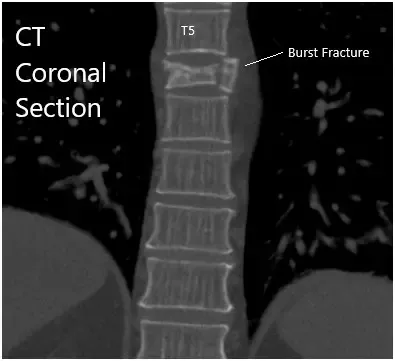

TAC Sagital y Cesárea coronal.

La TC reveló fractura aguda moderada por compresión de cuña asociada al cuerpo vertebral T6. La corteza posterior del cuerpo vertebral T6 se imprime ligeramente sobre el margen anterior del saco dural torácico. El hematoma mínimo se sitúa entre el cuerpo vertebral T6 y la pleura circundante.

Había una configuración normal de los cuerpos vertebrales torácicos restantes. Los espacios del disco torácico no están estrechados. No se demuestran protrufacciones discales posteriores ni hernias. El estrechamiento no está asociado con los forámenes neurales torácicos.